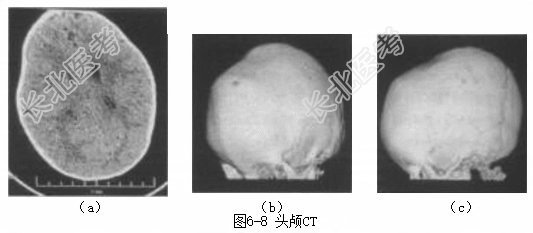

辅助检查头颅CT显示(图6-8)冠状缝及矢状缝基本闭合。诊断颅缝早闭。治疗完善三大常规、凝血功能、肝肾功能、电解质、乙肝两对半、HCV、HIV等检查。完善心电图、胸部X线片等术前评估。入院后完善相关检查,在全麻下行扩大颅缝再造十颅骨塑形术。